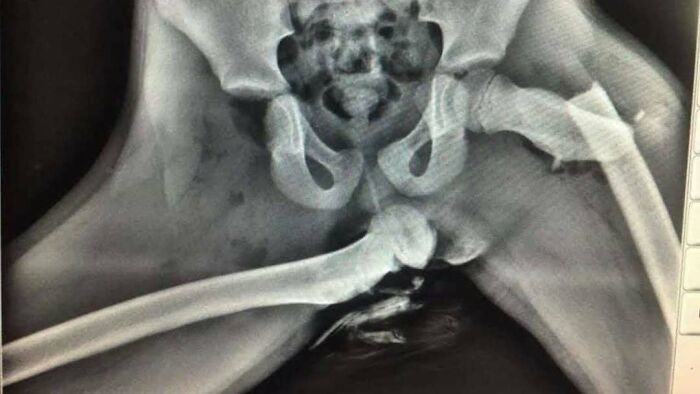

Mengapa Anda tidak boleh meletakkan kaki di dasbor mobil. Seorang wanita mengalami cedera mengerikan setelah meletakkan kakinya di dasbor mobil. Akibatnya, pinggulnya hancur. Foto: Boredpanda